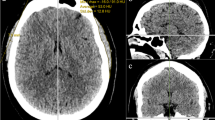

The Radiation was exposed for radiation therapy (Fig. 1) after breast cancer surgery and the volume of the affected breast areas (pectoralis major and pectoralis minor). We compare changes of the ratio of muscle after radiotherapy and confirm the effect. Three-dimensional (3D) muscle volume was measured to analyze changes in the volume of the breast muscle (pectoralis major and pectoralis minor) of patients who received radiation therapy after breast cancer surgery.

The FOV (Field Of View) concept in radiotherapy after breast cancer surgery.

Step 1. Whole muscle and bone: Semi-automatic Segmentation of the whole muscle areas including bone areas and Bone areas with HU (Hounsfield Unit) value

Segmentation of Whole muscle and bone by HU(Hounsfield Unit) value: (a) anterior view, (b)posterior view, (c) Left view.

The HU(Hounsfield Unit) values used in the first phase of the semi-automatic segmentation of muscles and bones are expressed in intensity value, and the segmentation process is carried out by dividing the range of values including both the muscle and the bone domain (Fig. 2a–c).